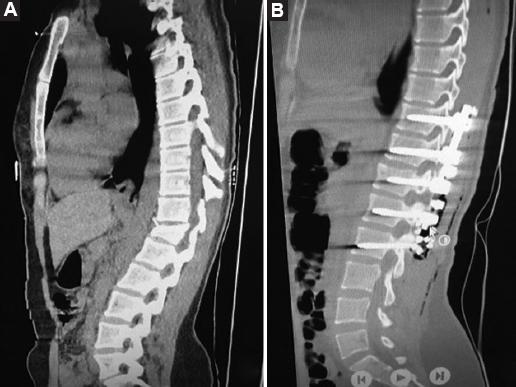

A retrospective review of 98 patients who underwent posterior stabilization surgery with a posterior approach in our clinic between 2018 and 2023 was conducted. The patients were divided into two groups based on the type of implant used: Those with PLSRR (Group 1, Fig. 1) and those with PLSDR (Group 2, Fig. 2).

For Group 1, patients were first positioned in the prone position and a midline incision was made, passing through the skin and subcutaneous layers. Bone structures were exposed through blunt muscle dissection. Under fluoroscopy guidance, pedicle screws were appropriately placed. The rigid rod system was locked to the pedicle screws. Procedures such as laminectomy, hemilaminectomy, or facetectomy were performed for decompression. Discectomy was applied to some patients. Fusion was performed for patients using allogeneic and autologous bone grafts, 5 cc for each level. Decortication was applied to the bones to expand the fusion area (Fig. 4)10,11.